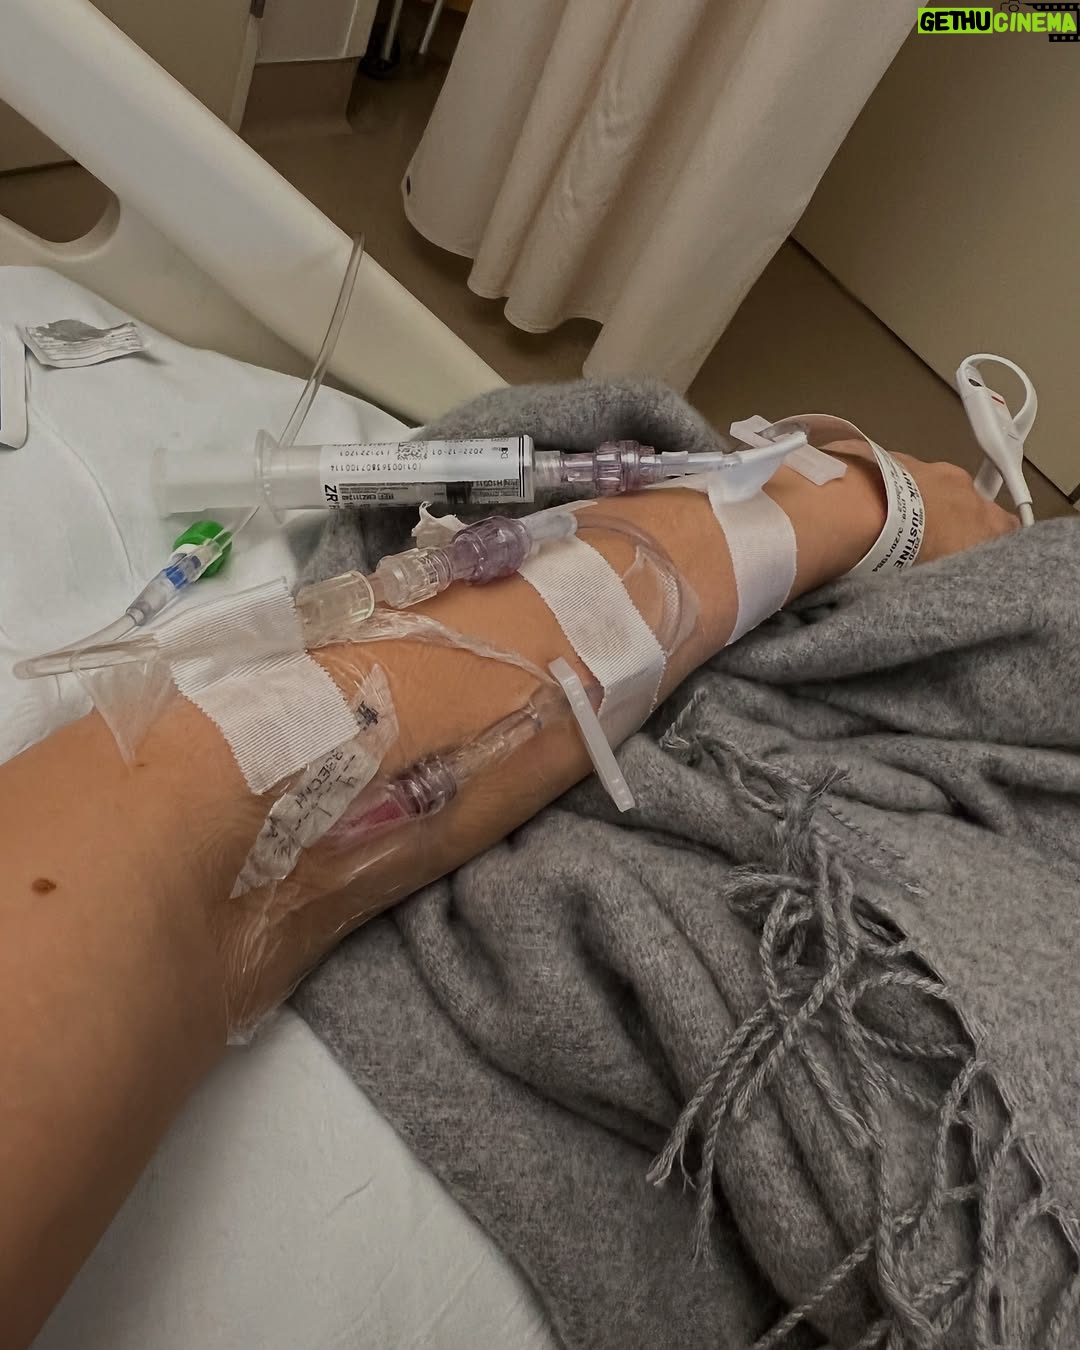

26.4K Likes – Justine Ezarik Instagram

Caption : OLD PHOTOS!! I am ok now!! Just my yearly reminder to you all that blood clots can be fatal! KNOW THE SIGNS, symptoms and if you’re possibly at risk. 3 years ago today there was a point that I wasn’t sure I’d make it but very grateful for the amazing care from doctors, support from friends and my sister who was there pretty much 24/7 with me! Thx @jennaezarik !! My diagnosis is thoracic outlet syndrome but there are many things that can lead to blood clots. Like prolonged immobility (long flights!), surgery, cancer, smoking, pregnancy, hormonal birth control, family history, obesity, age, genetic disorders and more. Signs and symptoms can vary depending on the location. Pain, swelling, redness, shortness of breath (if the clot travels to your lungs), headaches, weakness, numbness, difficulty speaking (it clot has traveled to your brain). Basically if you THINK something is wrong, don’t wait to seek help. I waited a few days after first noticing symptoms but brushed it off because I was “busy” 😳 I definitely won’t do that again! I have had to alter some activities I do to avoid possible repercussions but for the most part I am back and doing more than I ever have before! Took awhile to get back to this point but worth it 🙏🏻🩸Likes : 26432

26.4K Likes – Justine Ezarik Instagram

Caption : OLD PHOTOS!! I am ok now!! Just my yearly reminder to you all that blood clots can be fatal! KNOW THE SIGNS, symptoms and if you’re possibly at risk. 3 years ago today there was a point that I wasn’t sure I’d make it but very grateful for the amazing care from doctors, support from friends and my sister who was there pretty much 24/7 with me! Thx @jennaezarik !! My diagnosis is thoracic outlet syndrome but there are many things that can lead to blood clots. Like prolonged immobility (long flights!), surgery, cancer, smoking, pregnancy, hormonal birth control, family history, obesity, age, genetic disorders and more. Signs and symptoms can vary depending on the location. Pain, swelling, redness, shortness of breath (if the clot travels to your lungs), headaches, weakness, numbness, difficulty speaking (it clot has traveled to your brain). Basically if you THINK something is wrong, don’t wait to seek help. I waited a few days after first noticing symptoms but brushed it off because I was “busy” 😳 I definitely won’t do that again! I have had to alter some activities I do to avoid possible repercussions but for the most part I am back and doing more than I ever have before! Took awhile to get back to this point but worth it 🙏🏻🩸Likes : 26432

26.4K Likes – Justine Ezarik Instagram

Caption : OLD PHOTOS!! I am ok now!! Just my yearly reminder to you all that blood clots can be fatal! KNOW THE SIGNS, symptoms and if you’re possibly at risk. 3 years ago today there was a point that I wasn’t sure I’d make it but very grateful for the amazing care from doctors, support from friends and my sister who was there pretty much 24/7 with me! Thx @jennaezarik !! My diagnosis is thoracic outlet syndrome but there are many things that can lead to blood clots. Like prolonged immobility (long flights!), surgery, cancer, smoking, pregnancy, hormonal birth control, family history, obesity, age, genetic disorders and more. Signs and symptoms can vary depending on the location. Pain, swelling, redness, shortness of breath (if the clot travels to your lungs), headaches, weakness, numbness, difficulty speaking (it clot has traveled to your brain). Basically if you THINK something is wrong, don’t wait to seek help. I waited a few days after first noticing symptoms but brushed it off because I was “busy” 😳 I definitely won’t do that again! I have had to alter some activities I do to avoid possible repercussions but for the most part I am back and doing more than I ever have before! Took awhile to get back to this point but worth it 🙏🏻🩸Likes : 26432

26.4K Likes – Justine Ezarik Instagram

Caption : OLD PHOTOS!! I am ok now!! Just my yearly reminder to you all that blood clots can be fatal! KNOW THE SIGNS, symptoms and if you’re possibly at risk. 3 years ago today there was a point that I wasn’t sure I’d make it but very grateful for the amazing care from doctors, support from friends and my sister who was there pretty much 24/7 with me! Thx @jennaezarik !! My diagnosis is thoracic outlet syndrome but there are many things that can lead to blood clots. Like prolonged immobility (long flights!), surgery, cancer, smoking, pregnancy, hormonal birth control, family history, obesity, age, genetic disorders and more. Signs and symptoms can vary depending on the location. Pain, swelling, redness, shortness of breath (if the clot travels to your lungs), headaches, weakness, numbness, difficulty speaking (it clot has traveled to your brain). Basically if you THINK something is wrong, don’t wait to seek help. I waited a few days after first noticing symptoms but brushed it off because I was “busy” 😳 I definitely won’t do that again! I have had to alter some activities I do to avoid possible repercussions but for the most part I am back and doing more than I ever have before! Took awhile to get back to this point but worth it 🙏🏻🩸Likes : 26432

26.4K Likes – Justine Ezarik Instagram

Caption : OLD PHOTOS!! I am ok now!! Just my yearly reminder to you all that blood clots can be fatal! KNOW THE SIGNS, symptoms and if you’re possibly at risk. 3 years ago today there was a point that I wasn’t sure I’d make it but very grateful for the amazing care from doctors, support from friends and my sister who was there pretty much 24/7 with me! Thx @jennaezarik !! My diagnosis is thoracic outlet syndrome but there are many things that can lead to blood clots. Like prolonged immobility (long flights!), surgery, cancer, smoking, pregnancy, hormonal birth control, family history, obesity, age, genetic disorders and more. Signs and symptoms can vary depending on the location. Pain, swelling, redness, shortness of breath (if the clot travels to your lungs), headaches, weakness, numbness, difficulty speaking (it clot has traveled to your brain). Basically if you THINK something is wrong, don’t wait to seek help. I waited a few days after first noticing symptoms but brushed it off because I was “busy” 😳 I definitely won’t do that again! I have had to alter some activities I do to avoid possible repercussions but for the most part I am back and doing more than I ever have before! Took awhile to get back to this point but worth it 🙏🏻🩸Likes : 26432

26.4K Likes – Justine Ezarik Instagram

Caption : OLD PHOTOS!! I am ok now!! Just my yearly reminder to you all that blood clots can be fatal! KNOW THE SIGNS, symptoms and if you’re possibly at risk. 3 years ago today there was a point that I wasn’t sure I’d make it but very grateful for the amazing care from doctors, support from friends and my sister who was there pretty much 24/7 with me! Thx @jennaezarik !! My diagnosis is thoracic outlet syndrome but there are many things that can lead to blood clots. Like prolonged immobility (long flights!), surgery, cancer, smoking, pregnancy, hormonal birth control, family history, obesity, age, genetic disorders and more. Signs and symptoms can vary depending on the location. Pain, swelling, redness, shortness of breath (if the clot travels to your lungs), headaches, weakness, numbness, difficulty speaking (it clot has traveled to your brain). Basically if you THINK something is wrong, don’t wait to seek help. I waited a few days after first noticing symptoms but brushed it off because I was “busy” 😳 I definitely won’t do that again! I have had to alter some activities I do to avoid possible repercussions but for the most part I am back and doing more than I ever have before! Took awhile to get back to this point but worth it 🙏🏻🩸Likes : 26432

26.4K Likes – Justine Ezarik Instagram

Caption : OLD PHOTOS!! I am ok now!! Just my yearly reminder to you all that blood clots can be fatal! KNOW THE SIGNS, symptoms and if you’re possibly at risk. 3 years ago today there was a point that I wasn’t sure I’d make it but very grateful for the amazing care from doctors, support from friends and my sister who was there pretty much 24/7 with me! Thx @jennaezarik !! My diagnosis is thoracic outlet syndrome but there are many things that can lead to blood clots. Like prolonged immobility (long flights!), surgery, cancer, smoking, pregnancy, hormonal birth control, family history, obesity, age, genetic disorders and more. Signs and symptoms can vary depending on the location. Pain, swelling, redness, shortness of breath (if the clot travels to your lungs), headaches, weakness, numbness, difficulty speaking (it clot has traveled to your brain). Basically if you THINK something is wrong, don’t wait to seek help. I waited a few days after first noticing symptoms but brushed it off because I was “busy” 😳 I definitely won’t do that again! I have had to alter some activities I do to avoid possible repercussions but for the most part I am back and doing more than I ever have before! Took awhile to get back to this point but worth it 🙏🏻🩸Likes : 26432

26.4K Likes – Justine Ezarik Instagram

Caption : OLD PHOTOS!! I am ok now!! Just my yearly reminder to you all that blood clots can be fatal! KNOW THE SIGNS, symptoms and if you’re possibly at risk. 3 years ago today there was a point that I wasn’t sure I’d make it but very grateful for the amazing care from doctors, support from friends and my sister who was there pretty much 24/7 with me! Thx @jennaezarik !! My diagnosis is thoracic outlet syndrome but there are many things that can lead to blood clots. Like prolonged immobility (long flights!), surgery, cancer, smoking, pregnancy, hormonal birth control, family history, obesity, age, genetic disorders and more. Signs and symptoms can vary depending on the location. Pain, swelling, redness, shortness of breath (if the clot travels to your lungs), headaches, weakness, numbness, difficulty speaking (it clot has traveled to your brain). Basically if you THINK something is wrong, don’t wait to seek help. I waited a few days after first noticing symptoms but brushed it off because I was “busy” 😳 I definitely won’t do that again! I have had to alter some activities I do to avoid possible repercussions but for the most part I am back and doing more than I ever have before! Took awhile to get back to this point but worth it 🙏🏻🩸Likes : 26432